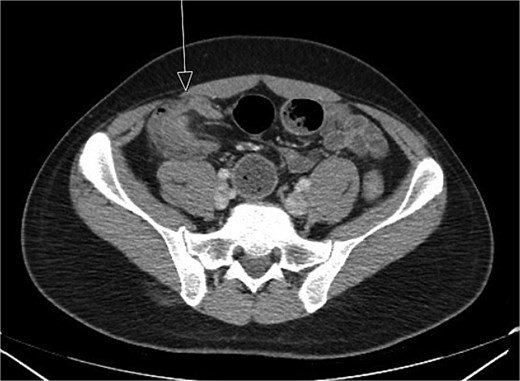

CT imaging (Figs 1 and 2) revealed an abnormal ileocolic configuration with intussusception of the distal ileal loop through the cecum. At this point, the general surgery team was consulted for immediate evaluation. Due to the history, physical exam, and findings identified on CT imaging, the patient was recommended to undergo exploratory laparotomy with intent, at minimum, to reduce the intussusception and likely perform a segmental small bowel resection to address his small bowel obstruction. Right hemicolectomy, however, was also discussed due to the patient’s family history of colon cancer to relieve the intussusception, which was causing a high-grade small bowel obstruction. During surgical exploration, the ileum was fixed within the colon, and the intussusception could not be reduced with gentle manipulation. This area of the ileum was significantly firmer than other areas, which was concerning for an ileal mass. The decision was made to resect this portion of the ileum and perform a right hemicolectomy with ileocolonic side-to-side anastomosis. The specimen was sent to pathology for further investigation. Postoperatively, the patient was hospitalized for 3 days for pain control and monitoring. He recovered in the hospital without further incident and was discharged on day 3 prior to the finalization of his pathology report.

Initial CT imaging, axial cut, showed an abnormal ileocolic configuration with intussusception of the distal ileal loop through the cecum.